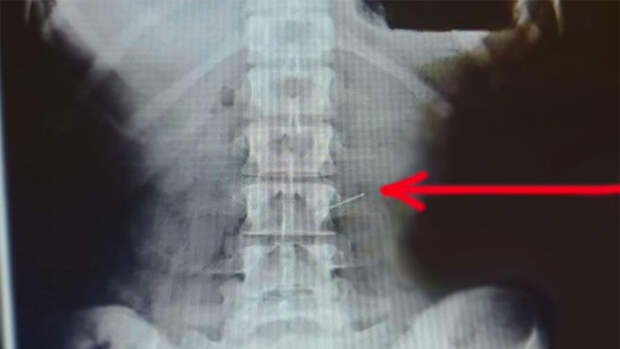

В больнице было установлено, что игла находилась в желудке.В пресс-службе медучреждения напомнили, что проглотившему иглу или булавку, нужно как можно меньше менять положение тела, чтобы предотвратить ее перемещение. Категорически противопоказаны любые резкие движения и наклоны, прием пищи и жидкости.

Хирургам потребовалось около часа, чтобы специальным зажимом "поймать" булавку и достать, не повредив при этом желудок и стенки пищевода.